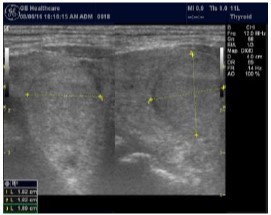

Parathyroid Glands Pathology:

In our study many patients were found to have nodules look very much like PT adenoma, Figure 7 below. At least, 4 patients were subsequently confirmed to have parathyroid adenomas, Figure 8 and 2 patients underwent surgery

Despite the fact that nodular pathology was found to be very prevalent among our study population, it has been found difficult to differentiate between thyroid and parathyroid pathology using ultrasound alone. However, some characteristics of the parathyroid glands might suggest parathyroid pathology in the context of the clinical picture of secondary or tertiary hyperparathyroidism which is very prevalent in ESKD patients’ populations.

Figure 7.Thyroid nodule suspicious for Parathyroid adenoma due to its location

Thyroid nodule suspicious for Parathyroid adenoma due to its location

Figure 8.Nodule that proven to be a parathyroid adenoma, volume =5265 mm3

Nodule that proven to be a parathyroid adenoma, volume =5265 mm3

There are 4 parathyroid glands (2 superior, 2 inferior) imbedded within the thyroid gland. The parathyroid glands are bean-like shape and small (20-40 mg) 25. Sonographically, the parathyroid glands have the following features 25:

Hyperplastic glands: hypoechoic, volume <500 mm3.

Nodular glands: hypoechoic. Volume >500 mm3

Histologically, if the excised gland has volume <500 mm3 it is said to be hyperplastic and if the volume is more than 500 mm3 it is nodular hyperplasia in 80% of cases26. In secondary HPT, the increase in the volume of parathyroid glands is associated with increase in vascularity, as evident in Color Doppler imaging 27.